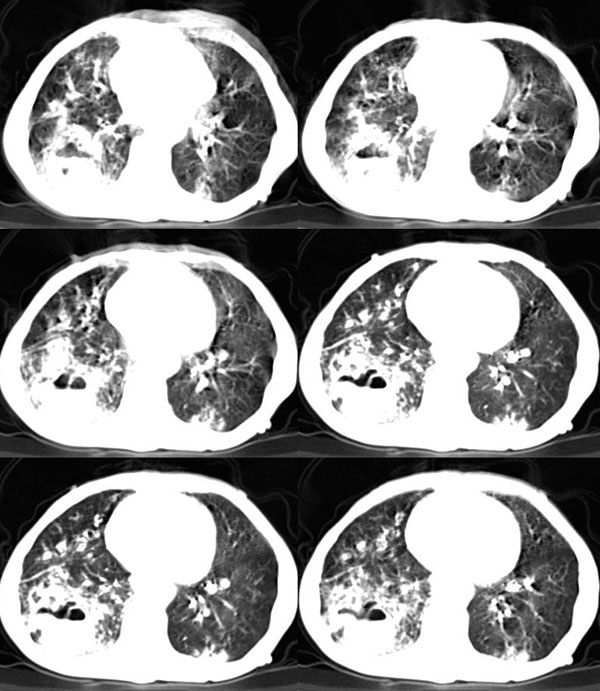

女:73岁;因一月前感冒后咳嗽,发烧,有大量脓痰,并且有恶臭味。

肺窗

补充_____伴双肺血行播散

考虑:1、右下肺脓肿;

2、支气管扩张合并感染。

意见:1,右下肺脓肿;

2,双下叶支气管扩张;

3,慢支并感染,肺气肿,肺心病;

4,肺间质纤维化.

该患者是我上个月作的,经正规抗炎治疗半月后平片显示吸收。{患者不愿ct复查}